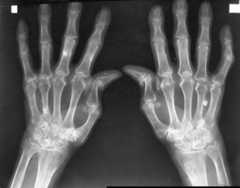

Radiograph of the hands in a patient with RA:

“Z” deformity shown in both thumbs and joint-space narrowing/bony erosion noted in CMC, MCP, and PIP joints